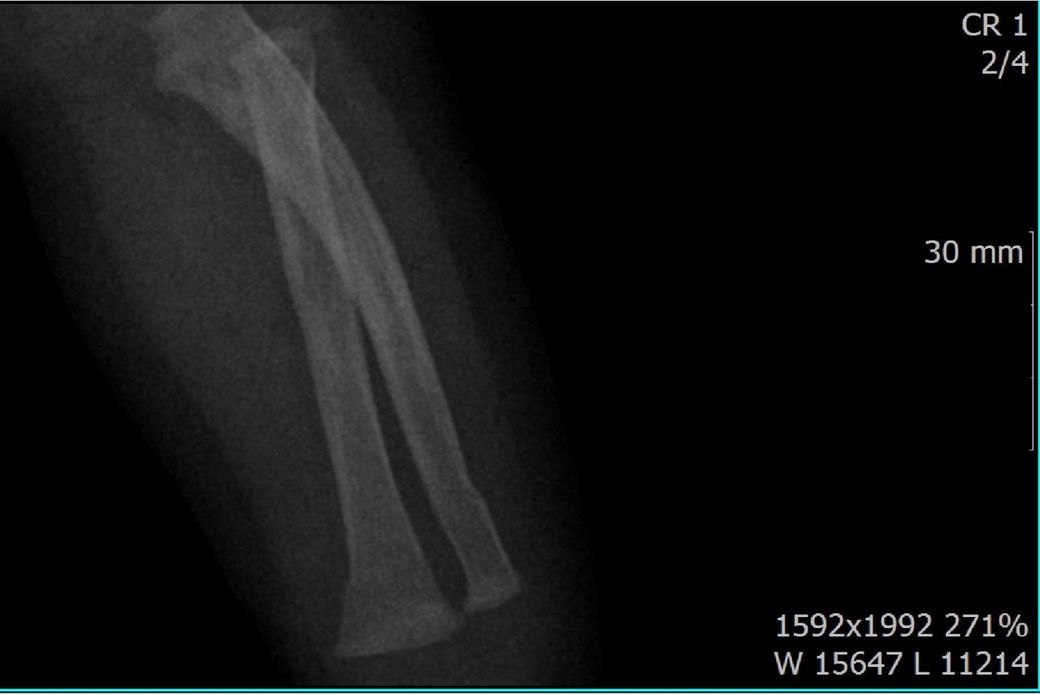

다름이 아니라, 첨부드린 엑스레이(X-ray) 사진처럼 골절 사실을 알게 되고 골절 발생 시점 대략적으로나마 추정시기를 파악하려고 문의 드리게 되었습니다

1) 3월 30일 촬영한 X-ray만으로 정확한 골절 시기를 100% 특정하는 데에는 한계가 있다는 점 충분히 인지하고 있기에 촬영날짜 기준으로 대략적으로 어느정도 시점에서 발생되었을 것으로 추측(ex 당일, 7~10일전, 7~14일 전, 10일 ~ 20일전, 14일 ~ 30일전 등등등)되는지 이해하고 싶습니다.

• 3번 째 사진

엑스레이 만으로 골절 발생 시기를 정확히 특정하긴 어렵지만 뼈의 염증 반응, 골막 반응, 골흡수 신생 정도를 통해 대략 추정은 가능합니다. 보통 급성 골절은 1~7일 이내, 골절선이 희미해지고 골막 반응이 보이면 10~20일 전후 뼈 융합이 일부 보이면 3~4주 이상 경과로 추정할 수 있습니다. 3월 30일 촬영 기준, 골절선의 형태와 신생골 유무에 따라 7~21일 내외의 외상으로 판단되는 경우가 많아요!

골절의 정확한 시기를 예측하기는 어려움이 있으나, 뼈의 골절선이 뚜렷하게 관찰된다면 0~7일 이내의 가능성이 있고 흐린 가골이 관찰되거나 골막의 일부 반응이 관찰된다면 7~14일 이내, 가골이 형성중인것이 관찰된다면 2-3주 이상의 골절시기를 대략적으로 유추해볼 수 있습니다.

골절의 상태를 보고 골절선이 선명하고 부위에 가골이 형성되지않았다면 보통 일주일 이내, 골절선이 보이지만 주변 부위에 가골이 조금씩 있다면 2주 이내, 골절선이 잘안보이고 가골이 보인다면 한달 이내로 판단 할 수 있습니다.

지금과 같이 엑스레이상 골절이 잘 보이는것으로 보아 2주 이내에 특별한 이슈가 있을만한지 생각해보시길 바랍니다^^